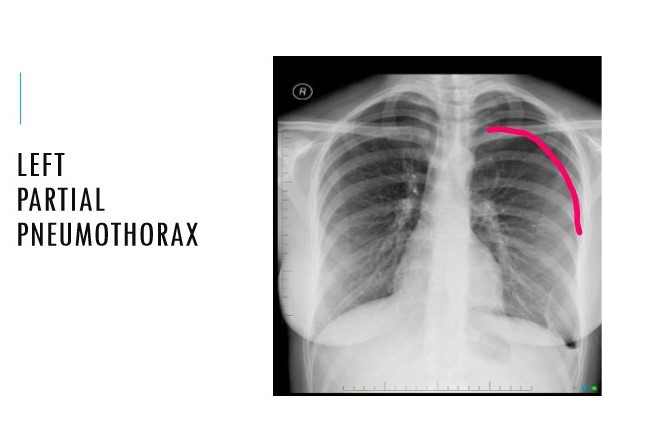

Define a pneumothorax

Air in the pleural space leading to lung collapse

Outline the different types of pneumothoraxes

**Spontaneous:** primary (normal lung) or secondary to pre-existing lung disease

Diagnosis?

Large left pneumothorax